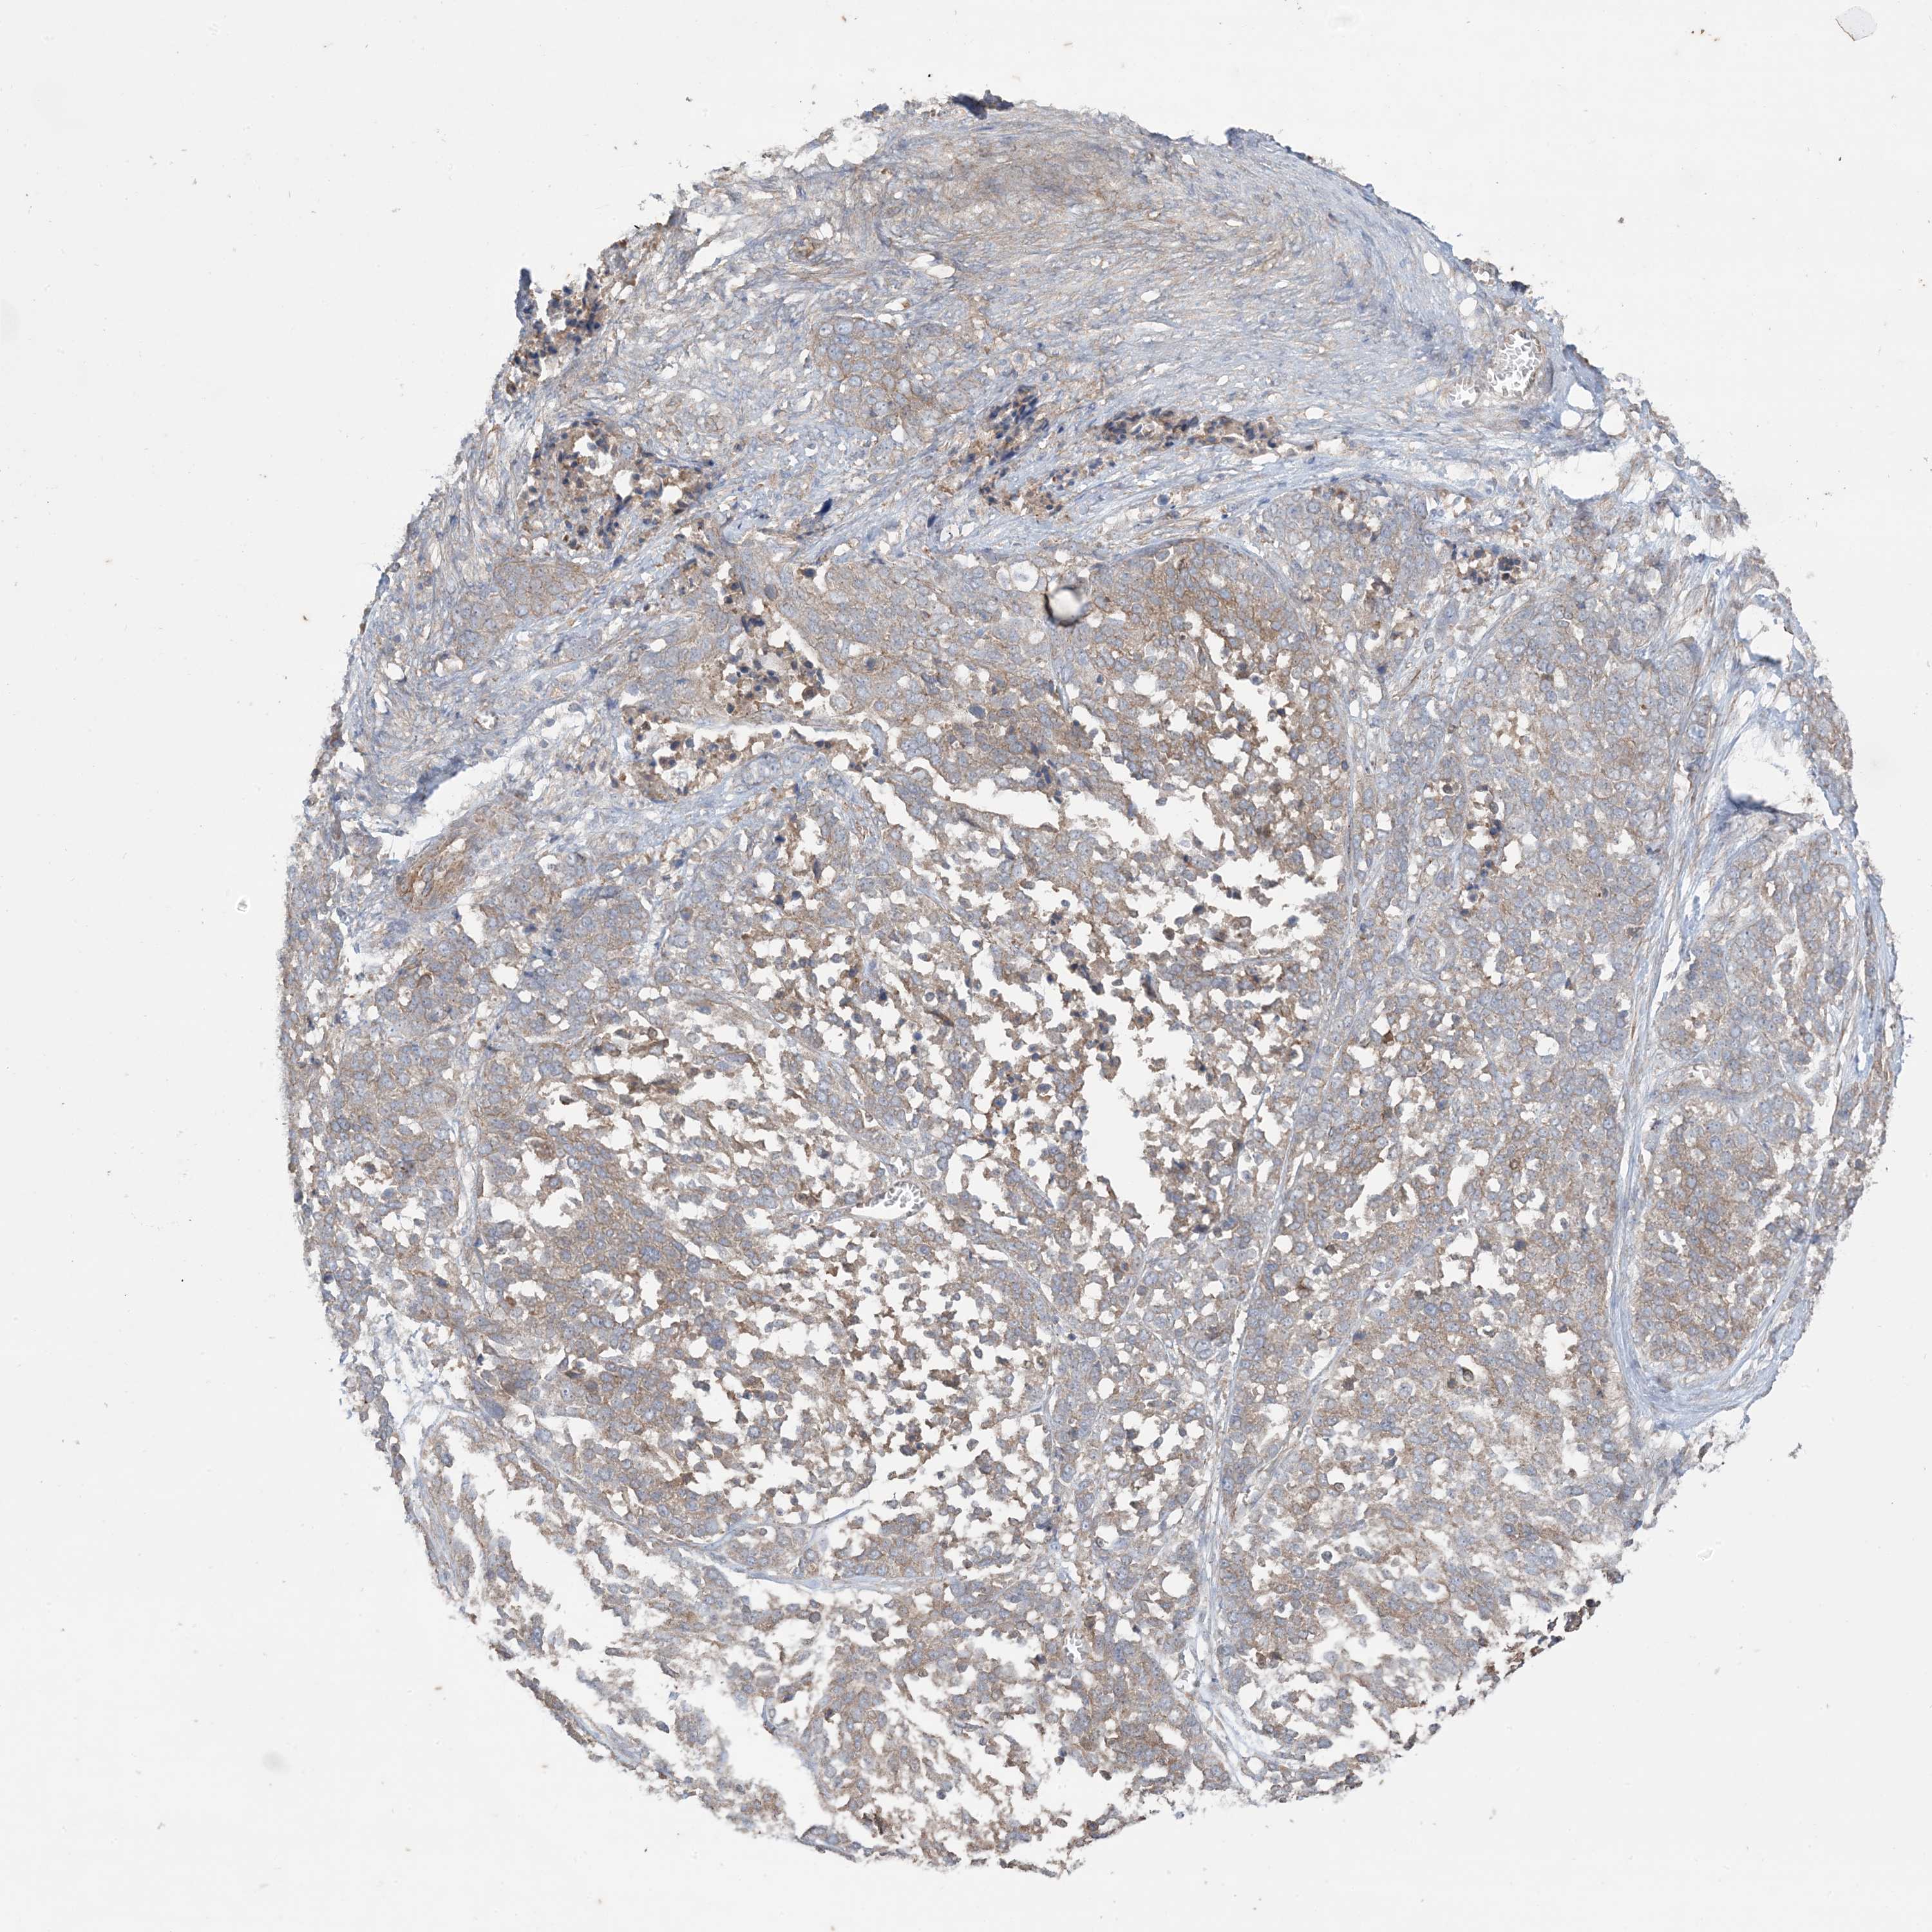

OVARIAN CANCER - Protein expressioni

A mouse-over function shows sample information and annotation data. Click on an image to view it in a full screen mode. Samples can be filtered based on level of antibody staining by selecting one or several of the following categories: high, medium, low and not detected. The assay and annotation is described here.

Note that samples used for immunohistochemistry by the Human Protein Atlas do not correspond to samples in the TCGA dataset.

Antibody stainingi

Antibody staining in the annotated cell types in the current human tissue is reported as not detected, low, medium, or high, based on conventional immunohistochemistry profiling in selected tissues. This score is based on the combination of the staining intensity and fraction of stained cells.

Each image is clickable and will lead to virtual microscopy that enables deeper exploration of all samples and also displays staining intensity scores, fraction scores and subcellular localization as well as patient and tissue information for each sample.

Antibody HPA036290

Staining

High

Medium

Low

Not detected

Intensity

Strong

Moderate

Weak

Negative

Quantity

>75%

75%-25%

<25%

None

Location

Nuclear

Cytoplasmic/membranous

Cytoplasmic/membranous,nuclear

Cystadenocarcinoma, serous, NOS

Carcinoma, endometroid

Cystadenocarcinoma, mucinous, NOS

Carcinoma, NOS